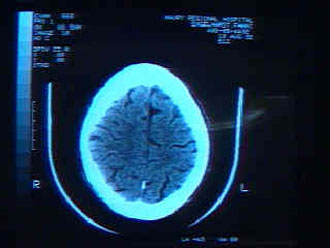

Σικάγο: Με επιτυχία στέφθηκε το εγχείρημα Αμερικανών επιστημόνων να διασφαλίσουν μέσω γενετικής μηχανικής τη γέννηση ενός μωρού, το οποίο δεν φέρει γονίδιο που ευθύνεται για πρόωρη εκδήλωση της νόσου Αλτσχάιμερ. Το μωρό είναι σήμερα 18 μηνών, ωστόσο οι συνθήκες της γέννησής του δημοσιοποιήθηκαν μόλις χθες, Τρίτη, εγείροντας ηθικά ερωτήματα για το ρόλο της γενετικής μηχανικής στην αναπαραγωγή.